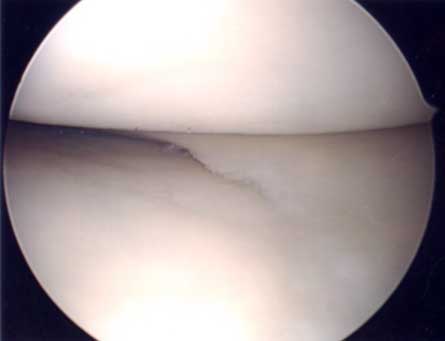

第2段階軟骨形成術

軟骨の剥離や亀裂が①より少し進んだ段階です。放っておくとさらに軟骨欠損が進み軟骨障害は広くなり且つ深くなります。この段階ではまだドリリングなどの操作は不要です。第3段階軟骨障害との間は幅広く関節鏡で見てみないと最終的に判断できません。この段階では手術結果は比較的よく平均75~90点ほどになります。